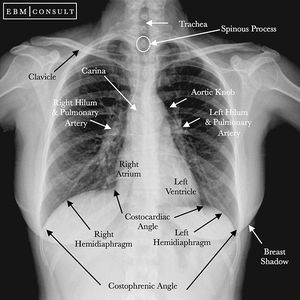

This is a labeled chest radiograph labeled as its is important to know the landmarks and its position to differentiate between different diseases and abnormal conditions. Please notice that the gastric bubble might have air that sometimes can be mixed with air under the diaphragm that is caused by perforation, so it is important to differentiate between them.